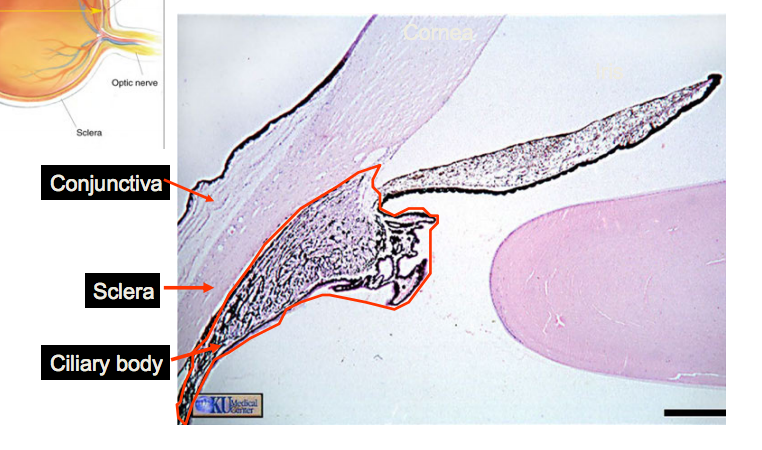

What is the anterior chamber angle?

Junction between iris and cornea, where aqueous humour drains out of eye

What are the key structures in the anterior chamber angle?

Cornea

Trabecular meshwork

Canal of Sclemm

Ciliary body

What are the important structures in the ciliary body?

Ciliary processes (ciliary epithelium)

Ciliary muscle

What are the functions of the ciliary body?

Formation of aqueous humour (ciliary epithelium)

Tethers lens (ciliary processes)

Accommodation (ciliary muscle)